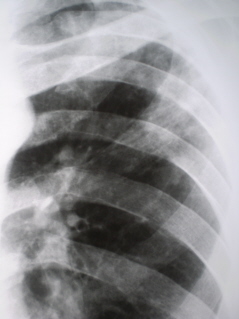

На обзорной рентгенограмме определяются, инфильтративные фокусы различной величины: от 1,5 см. в диаметре до поражения целой доли или сегмента, чаще всего в верхних отделах легких.

Туберкулезные инфильтраты локализуются большей частью в верхних отделах (I, IIи VIсегментах), а неспецифические воспалительные процессы –в средних и нижних полях.

От туберкулезного инфильтрата отходит «дорожка» к корню легкого; обычно по периферии основного фокуса поражения заметны отдельные очаговые тени, последние могут быть и в других участках этого же или противоположного легкого как результат бронхогенного обсеменения.

Интенсивность фокусов различная, большей частью они окаймлены нечетким, размытым контуром, имеют неправильную форму, негомогенную структуру.

При сегментарном и долевом поражении контуры инфильтрата будут четкими. В прилегающих участках легкого определяются очаги различной величины, сетчатость, тяжистость, воспалительная "дорожка" к корню.

Инфильтративно-пневмонический туберкулез легких осложняется распадам с формированием каверны. Она обнаруживается в виде просветления в инфильтрате, имеет округлую или неправильную форму, с четким внутренним контуром.